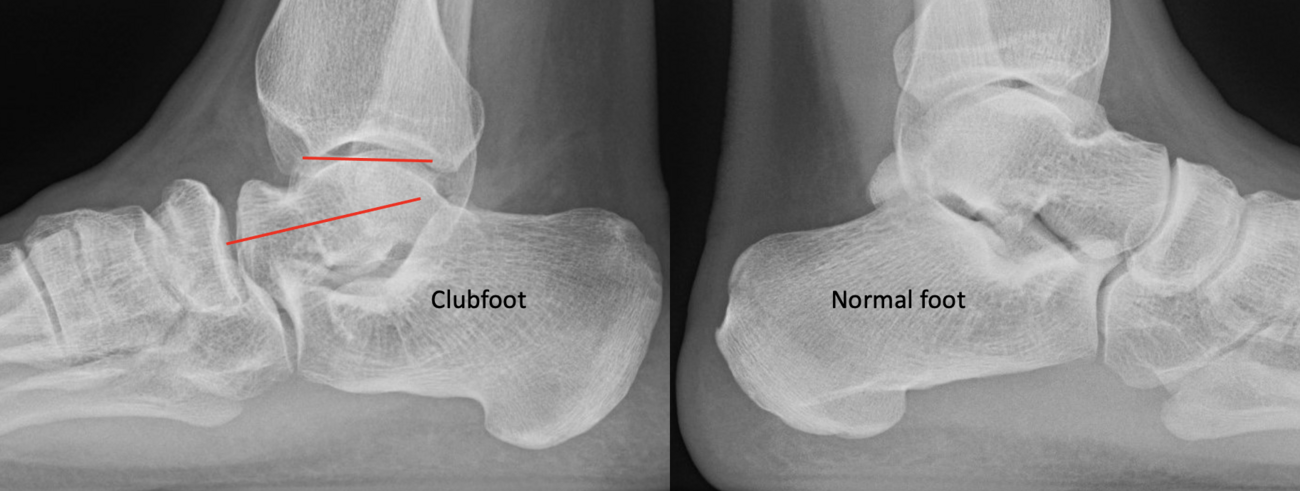

For 30 years, my colleague Col. (Ret) Kathy McHale, MD (pediatric orthopedist and former Army Orthopedic Consultant to the Surgeon General), and I studied and collected data on active-duty military personnel with clubfeet. She presented our data at the POSNA (Pediatric Orthopedic Society of North America) and SOMOS (Society Of Military Orthopedic Surgeons) meetings, and I presented my data at state meetings, but the data is as of yet unpublished. Between the two of us, we collected data on over 250 active duty military seen early or later on in their military career with congenital clubfeet. I am always amazed in my experience to see, how few physicians, let alone radiologists, understand the difference between what a normal and congenital clubfoot looks like as an adult.

As the Ponseti grew in popularity, I noted significant discrediting of surgical options. Well long-term studies on the Ponsetti are starting to surface, and it is not without its own problems. Kids are lost to follow-up, not braced appropriately, and just like we saw in long-term studies with the posteromedial release, there is a lot of undercorrection. Casting cannot and will not ever achieve what the Cincinnati release can. Although the Ponseti may not have the complications of the Cincinnati, X-ray data reveals that the Ponseti cannot and does not correct everything, most critically, talocalcaneal angles. You can not solve a clubfoot with an Achilles tenotomy and an overly aggressive casting. As these kids develop, I see residual met adductus and calcaneal varus, along with casting complications like flat top talus and met primus elevatus. I then see that they will develop DJD just like posteriomedial and Cincinnati releases. Haasbeck and team in 1997 reported that the Cincinnatti required fewer procedures than the posteromedial release over the life of their study.14 Thomas performed a systematic review in 2019, concluding that the longer the study follow-up, the greater the relapse rate and the poorer the results of the Ponseti.15 For most of us who have done clubfeet surgery for many years, this is no surprise. Among the 46 studies meeting inclusion criteria, they saw as high as 67 percent required future surgeries to address relapse.15

So, to summarize, true congenital clubfeet have abnormal talar bodies, which lead to abnormal ankle and subtalar joints with short Achilles and tight posterior tibial tendons. Regardless of treatment, there is nothing anyone can do to make the talus a normal bone. Many of these cases can and will develop additional deformities. Only the Cincinnati release can address every issue associated with the deformity, but it is NOT a cure. The Ponseti procedure is a total compromise, also NOT a cure. The sooner everyone treats the Ponseti as a compromise, I believe we will be far happier with the outcomes. I remember discussing this with others treating pediatric orthopedic issues during the rise of the Ponseti in the early 2000s. We all agreed, undercorrecting the deformity will lead to more surgeries and residual deformities. Until we all face the reality that clubfeet are a genetic deformity and not just a positional deformity, we will never make them perfect. Thus, athletes and the military will put any and all clubfeet patients to the test. There is no doubt that exceptions exist, but in time, at least based on our limited review of over 1000 clubfeet and 250 cases we saw in the military, no one is immune to complications, arthritis, and ultimately disability.